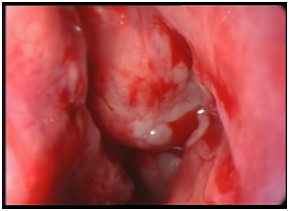

The patient was posted for endoscopic marsupialization of the mucoceles. The mucocele sac from ethmoid sinus was incised and the mucus was drained out (Figure 4 & 5) following which another mucocele sac was identified in the frontal sinus and was drained out (Figure 6 & 7) thus confirming the diagnosis of multiple mucocele introperately.

Figure 6 Intraoperative picture showing right frontal mucocele mucocele

Figure 7 Intraoperative picture showing right  frontal sinus after draining frontal.

Cleared frontal and ethoidal sinuses were examined thoroughly after drainage of the mucoceles (Figure 8). The patient symptoms were relieved postoperatively and the patient was discharged. On follow-up nasal endoscopy showed open sinus cavity, mucosa normal with healthy epithelialization without any sign of recurrence.

Figure 8 Intraoperative picture showing cleared ethoid and frontal sinuses.